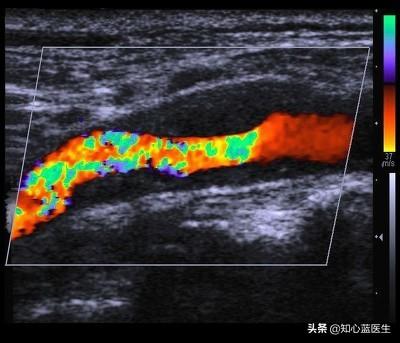

L'athérosclérose est une altération dégénérative des vaisseaux sanguins artériels. L'incidence de l'athérosclérose augmente progressivement avec l'âge, et il n'est pas exagéré de dire que la moitié des personnes âgées de plus de 60 ans sont atteintes d'athérosclérose. De nombreuses personnes ne présentent aucun symptôme et ne sont détectées que lorsqu'elles subissent des examens, tels que l'échographie carotidienne et l'échographie cardiaque. En ce qui concerne l'athérosclérose, je pense que les points suivants sont à connaître.

L'athérosclérose est en fait le dépôt de composants lipidiques de la circulation sanguine sous la paroi interne des artères.Il s'agit d'un processus qui peut être très complexe, comme des sédiments fins déposés sur les rives d'une rivière ou un tuyau métallique usagé depuis longtemps et couvert de rouille.

Plus la teneur en lipides du sang est élevée, en particulier le cholestérol LDL, plus le risque de dépôt de lipides sous les artères est grand, formant ainsi l'athérosclérose. Il existe également des facteurs qui favorisent le dépôt de lipides, tels que l'âge, l'hypertension artérielle, le diabète, le tabagisme, le manque d'exercice et l'obésité.